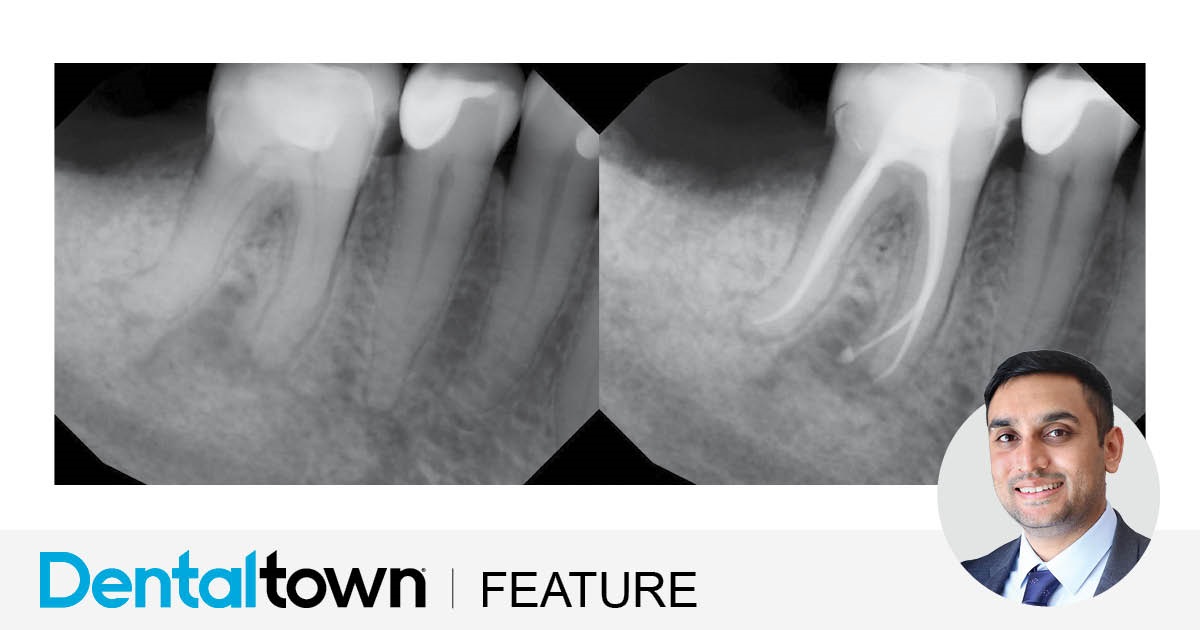

Clinical Case Spotlight: Efficient and Predictable Endodontics

Dr. Biraj Patel showcases an endodontic case that provided a streamlined, predictable and efficient treatment by utilizing EdgeFile X7 rotary files and EdgeBioCeramic Sealer.

by Dr. Biraj Patel

March 2025